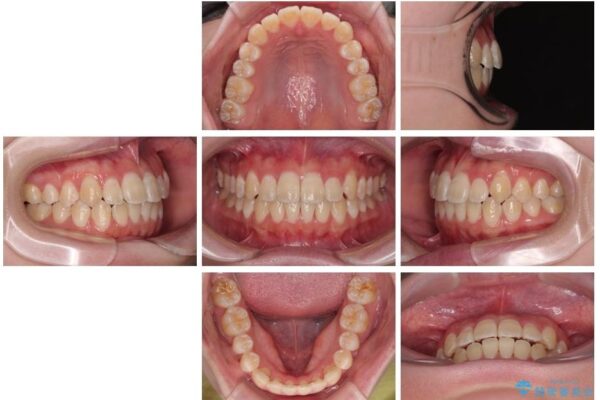

上下の正中(真ん中のライン)もずれることなく、バランスの取れた美しい歯並びに。笑顔に自信を持てる仕上がりとなりました。

治療後

• 【モニター】前歯のデコボコをスッキリ解消!目立ちにくいワイヤー矯正でスピーディに治療完了 治療後画像